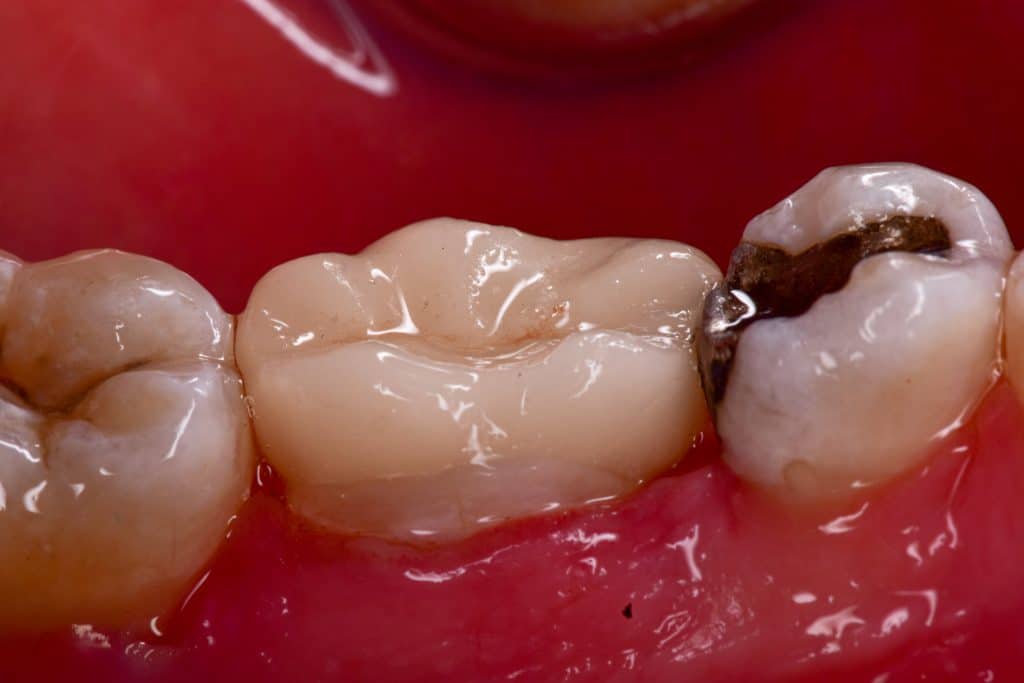

Buccal view

Immediate result , buccal view